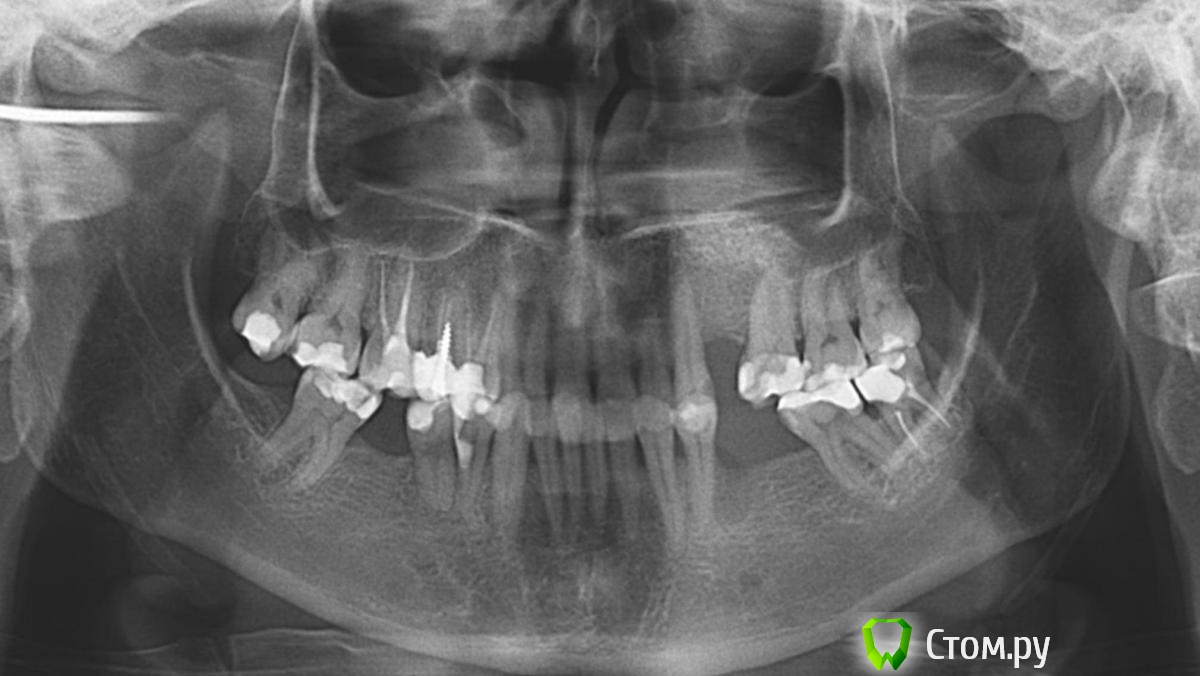

Необыкновенная Опубликовано 17 октября, 2014 Поделиться Опубликовано 17 октября, 2014 (изменено) Добрый день, уважаемые стоматологи!Прошу совета:Фото № 1 - рецессия десны на нижних зубах. Вопрос - что можно сделать? Что, в 2-х словах, представляет из себя методика / (операция) / варианты? Какова гарантия приживаемости? Надолго ли хватает? Фото № 2 - из-за той же рецессии и клиновидных дефектов, появилось оголение корней (конкретные на фото 4, 5, 6 - пойдут под коронки). У 6-ки корень красный (резорциновый вроде говорили?). Вопрос - т.к. после установки коронок будут видны корни из-за ушедшей десны, ВОЗМОЖНО ЛИ хирургически воссоздать нормальный десневой край и сосочки? Розовую керамическую десну не хочу ((Фото № 3 - ОПТГ - прилагаю на всякий случай, по кости вроде пока всё в норме. Или уже нет?(просьба не пугаться глубокой коричневой полосы на зубах, я не курю и посещаю гигиениста иногда )) - это тетрациклин, отбеливание не помогает (и больно). И просьба не пугаться скученности, ортодонтическое лечение было давно (всё вернулось), готовлюсь к протезированию. Спасибо всем заранее за рассмотрение вопроса и консультации!!! Изменено 17 октября, 2014 пользователем Необыкновенная Ссылка на комментарий

SDC Опубликовано 17 октября, 2014 Поделиться Опубликовано 17 октября, 2014 (изменено) Добрый день, уважаемые стоматологи!Прошу совета:Фото № 1 - рецессия десны на нижних зубах. Вопрос - что можно сделать? Что, в 2-х словах, представляет из себя методика / (операция) / варианты? Какова гарантия приживаемости? Надолго ли хватает? Фото № 2 - из-за той же рецессии и клиновидных дефектов, появилось оголение корней (конкретные на фото 4, 5, 6 - пойдут под коронки). У 6-ки корень красный (резорциновый вроде говорили?). Вопрос - т.к. после установки коронок будут видны корни из-за ушедшей десны, ВОЗМОЖНО ЛИ хирургически воссоздать нормальный десневой край и сосочки? Розовую керамическую десну не хочу ((Фото № 3 - ОПТГ - прилагаю на всякий случай, по кости вроде пока всё в норме. Или уже нет?(просьба не пугаться глубокой коричневой полосы на зубах, я не курю и посещаю гигиениста иногда )) - это тетрациклин, отбеливание не помогает (и больно). И просьба не пугаться скученности, ортодонтическое лечение было давно (всё вернулось), готовлюсь к протезированию. Спасибо всем заранее за рассмотрение вопроса и консультации!!!Фото № 1 Возможно закрыть множественные рецессии десны, желательно ортодонтическое лечение. В 2-х словах :подтяжка десны с утолщением биотипа за счет трансплантации слизисто-десневого трансплантата с неба. Хватает надолго. Гарантия - это означает, что доктор или клиника берет на себя обязательства по устранению осложнений и/или проведение повторной операции без доп. оплаты. Гарантировать реакцию Вашего организма доктор не может. Фото №2 нет необходимости в закрытии рецессии. Просто коронки на 4, 5, 6-й зубы. Межзубные сосочки в норме. Обнажение корней на 6-м зубе произошло за счет его выдвижения в сторону дефекта з. ряда на н.ч. На 4-м - дефект твердых тканей в пришеечной области скорее всего из-за перегрузки Фото № 3 С костной тканью в области зубов относительный порядок, есть необходимость в восстановлении непрерывности зубных рядов с применением имплантации. Изменено 17 октября, 2014 пользователем SDC Ссылка на комментарий